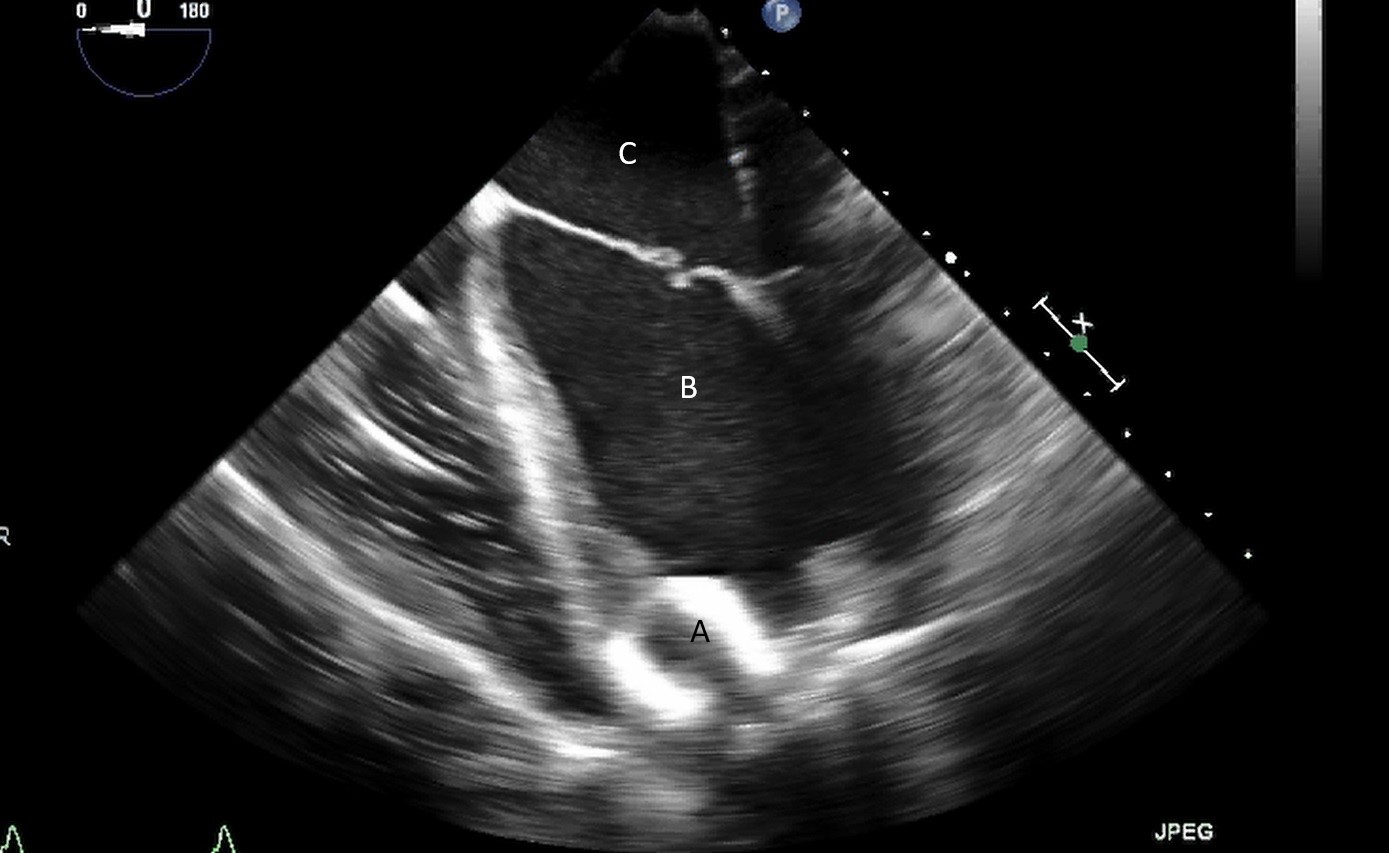

When examining the inflow cannula of the LVAD, the inflow cannula should be orientated and aligned with the mitral valve [47] (Figs. 19,20). Laminar flow from the ventricle to the device suggests a correctly aligned inflow cannula [56]. Obstruction of the inflow cannula manifests with increased turbulence and elevated doppler velocities [47].

Fig. 20.Transesophageal echocardiogram four chamber image with the LVAD inflow cannula pointing towards the septum (A). (B) LV (C) LA.